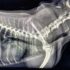

Zapadanie tchawicy u psów (TCS-Tracheal Collapse Syndrome)

Źródło: https://wetgliwice.pl/ Zapadanie tchawicy u psów (TCS-Tracheal Collapse Syndrome) Zapadanie tchawicy u psów (TCS-Tracheal Collapse Syndrome) jest przewlekłą chorobą układu oddechowego obserwowaną głównie u raz małych i miniaturowych (Yorkshire terrier, Szpic …